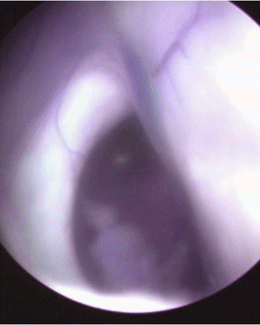

Endoscopic view of the left foramen of Monro

Endoscopically, the thalamostriate vein is located on the posterolateral aspect of the foramen of Monro [16]. During the procedure direct endoscopic vision of the obstructed foramen, careful perforation and fenestration of the slit and thin membrane as well as avoidance of injury to the deep drainage veins surrounding the foramen of Monro are all important for a successful outcome.